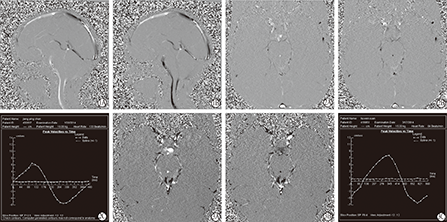

矢状位PC-Cine序列示在一个心动周期内桥前池、延前池、中脑导水管、四脑室内CSF呈渐明渐暗的循环变化,心脏收缩期峰流速方向向下,舒张期方向向上,峰流速曲线为规则或基本规则的正弦或余弦曲线。

从<1.5岁组小儿脑脊液流动成像中可见,PC-Cine图像中,中脑导水管在收缩期显示为高信号,在舒张期显示为低信号,收缩期(向下)及舒张期(向上)峰流速分别为6.42 cm/s和5.58 cm/s(图2)。1.5~14岁组小儿脑脊液流动成像中可见,PC-Cine图像中,中脑导水管在收缩期亦显示为高信号,在舒张期显示为低信号,收缩期(向下)及舒张期(向上)峰流速分别为7.80 cm/s和7.56 cm/s(图3)。脑脊液中脑导水管处向下及向上峰流速<1.5岁组均较1.5~14岁组慢,差异均有统计学意义(P<0.05)。<1.5岁组净流量为(0.001±0.001)ml/cycle,较1.5~14岁组(0.002±0.003)ml/cycle少,但组间差异无统计学意义(P>0.05,表1)。